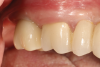

Fig 9. Final screw-retained implant

crown 3 years postoperative.

Figure 9

Fig 15. Final zirconia restoration.

Figure 15